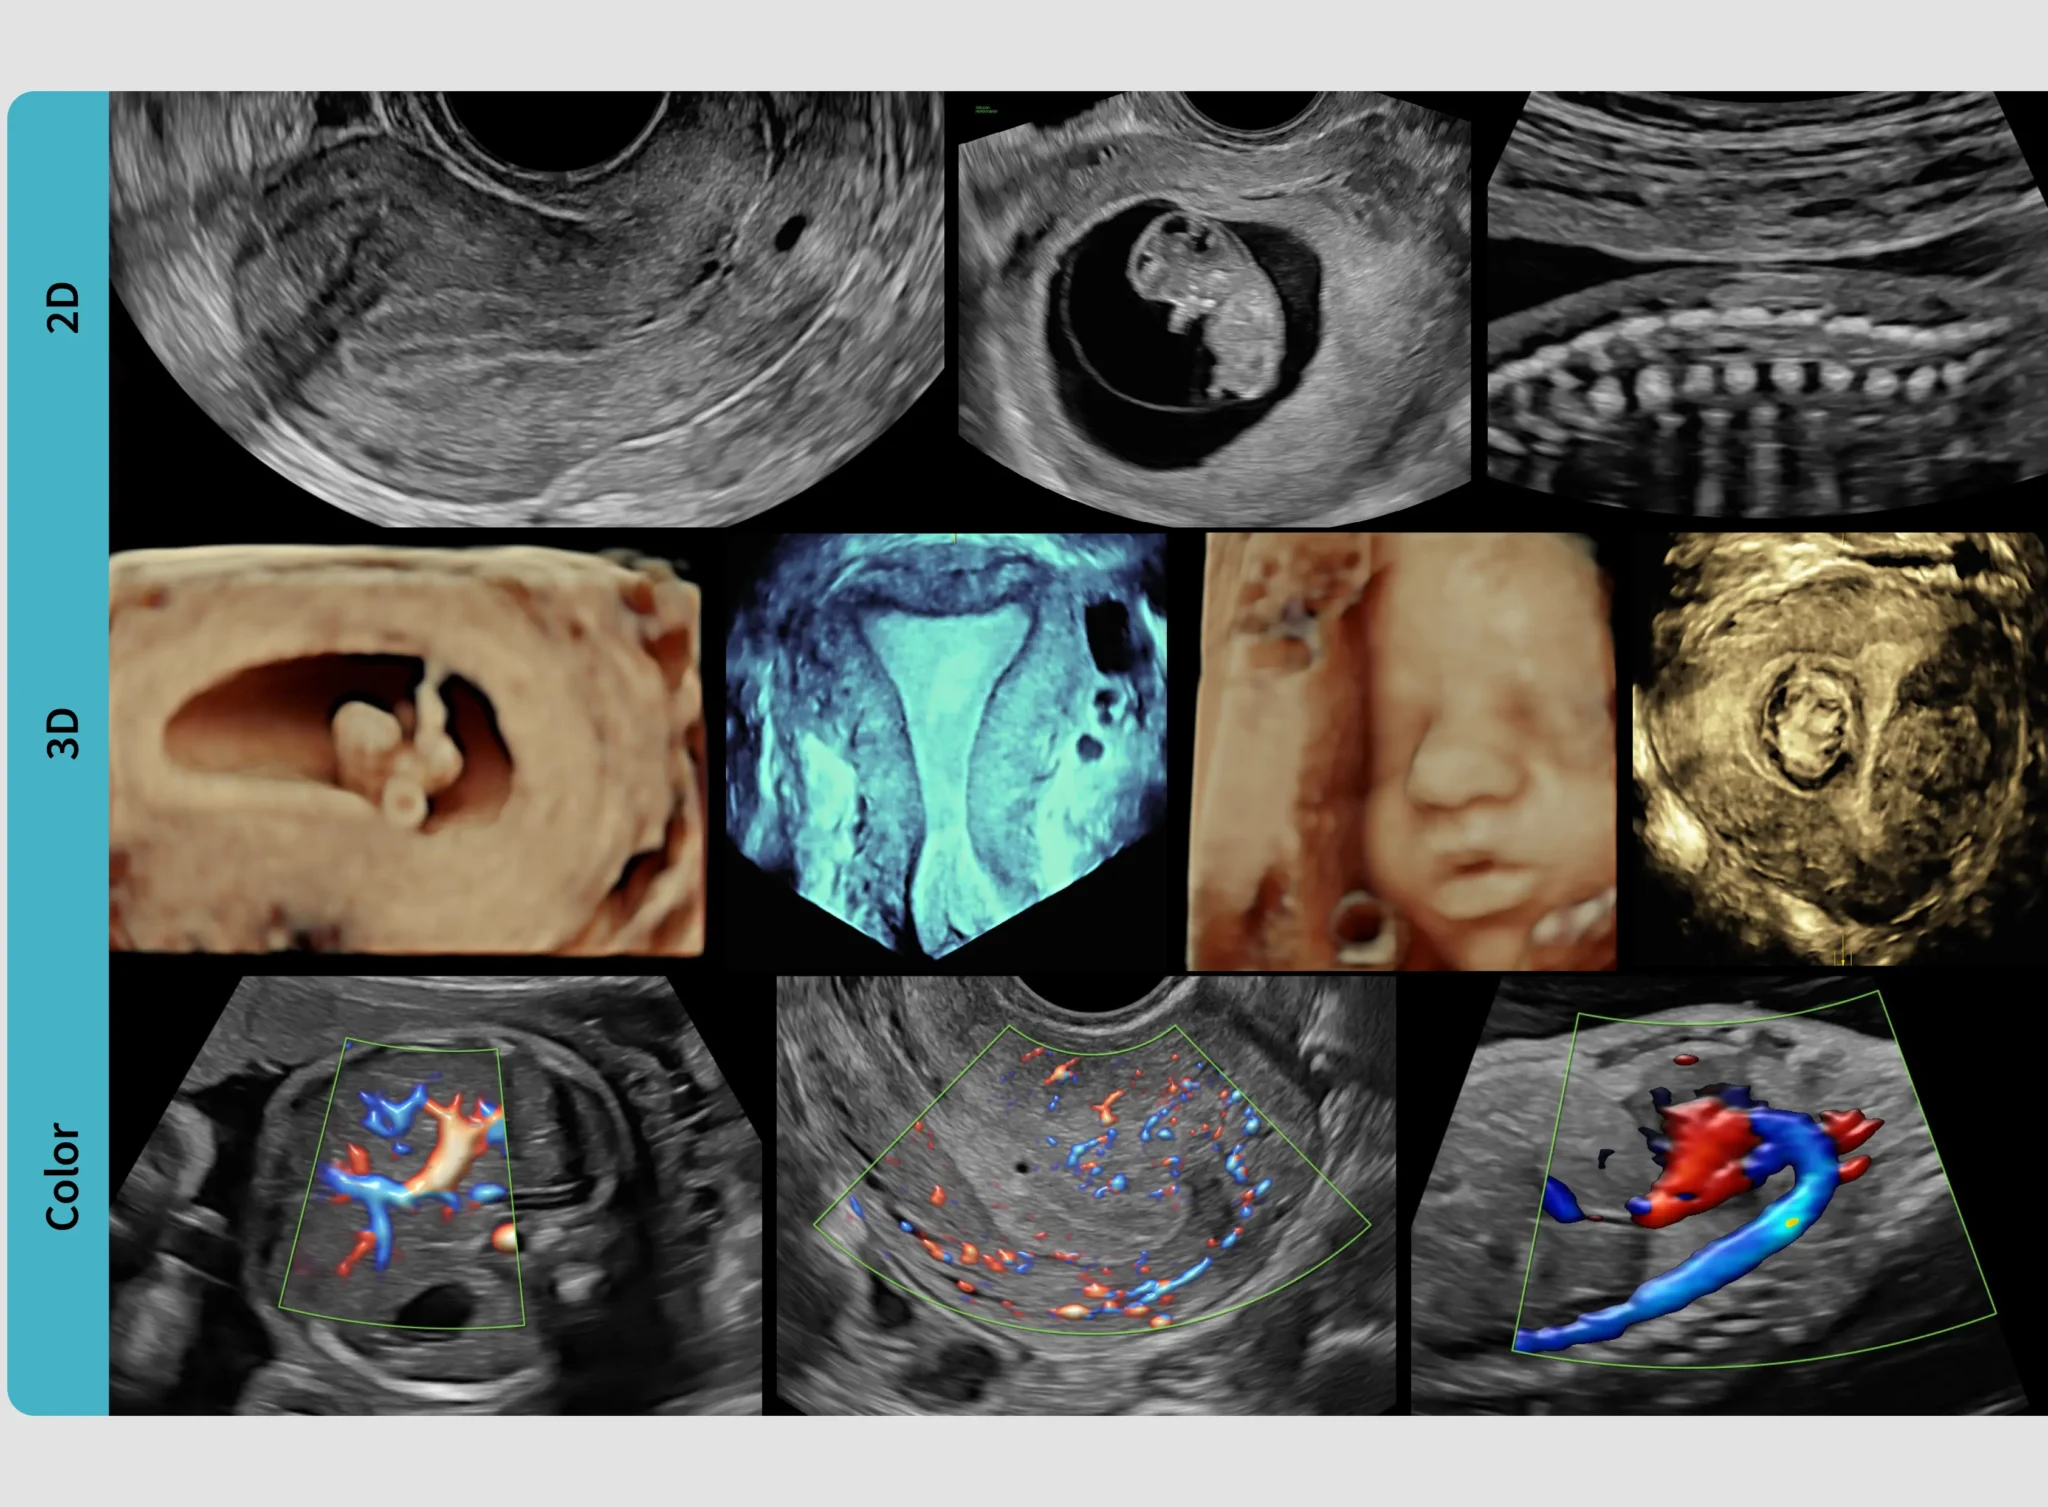

En Eco Love apostamos por la tecnología más avanzada para ofrecerte una experiencia emocional única y segura durante el embarazo. Nuestro ecógrafo Voluson Performance 18 nos permite mostrarte imágenes hiperrealistas de tu bebé, con un nivel de detalle y naturalidad nunca visto en Elda y comarca. Descubre cómo la innovación puede transformar tu recuerdo para siempre.

El sistema Voluson incorpora inteligencia artificial que permite optimizar cada imagen y reducir el tiempo de exploración, lo que se traduce en una experiencia más fluida y centrada en lo emocional:

Auto-calibración y mejora de imagen automática

Control por voz: nuestro equipo puede ajustar parámetros sin interrumpir el momento

Shadow reduction: elimina sombras para revelar detalles ocultos

Radiantflow™: visualiza hasta los vasos sanguíneos más pequeños con precisión